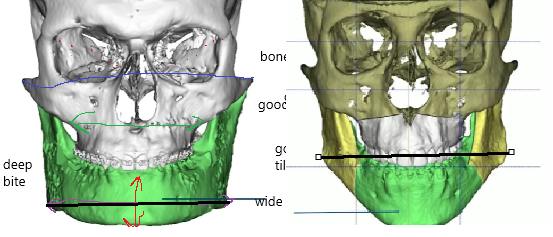

1. You need to have decent jaw width(black) at the gonions( wide jaw), both good examples, right has outward gonions(unfortunate he has short ramus), jaw implants look shit so over if you dont have.

2. Good vertical height across the whole mandible(long ramus big part of it), but if you got too much you will be ogre( very bad). black box is good, red bad:

1. You need to have decent jaw width(black) at the gonions( wide jaw), both good examples, right has outward gonions(unfortunate he has short ramus), jaw implants look shit so over if you dont have.

2. Good vertical height across the whole mandible(long ramus big part of it), but if you got too much you will be ogre( very bad). black box is good, red bad: